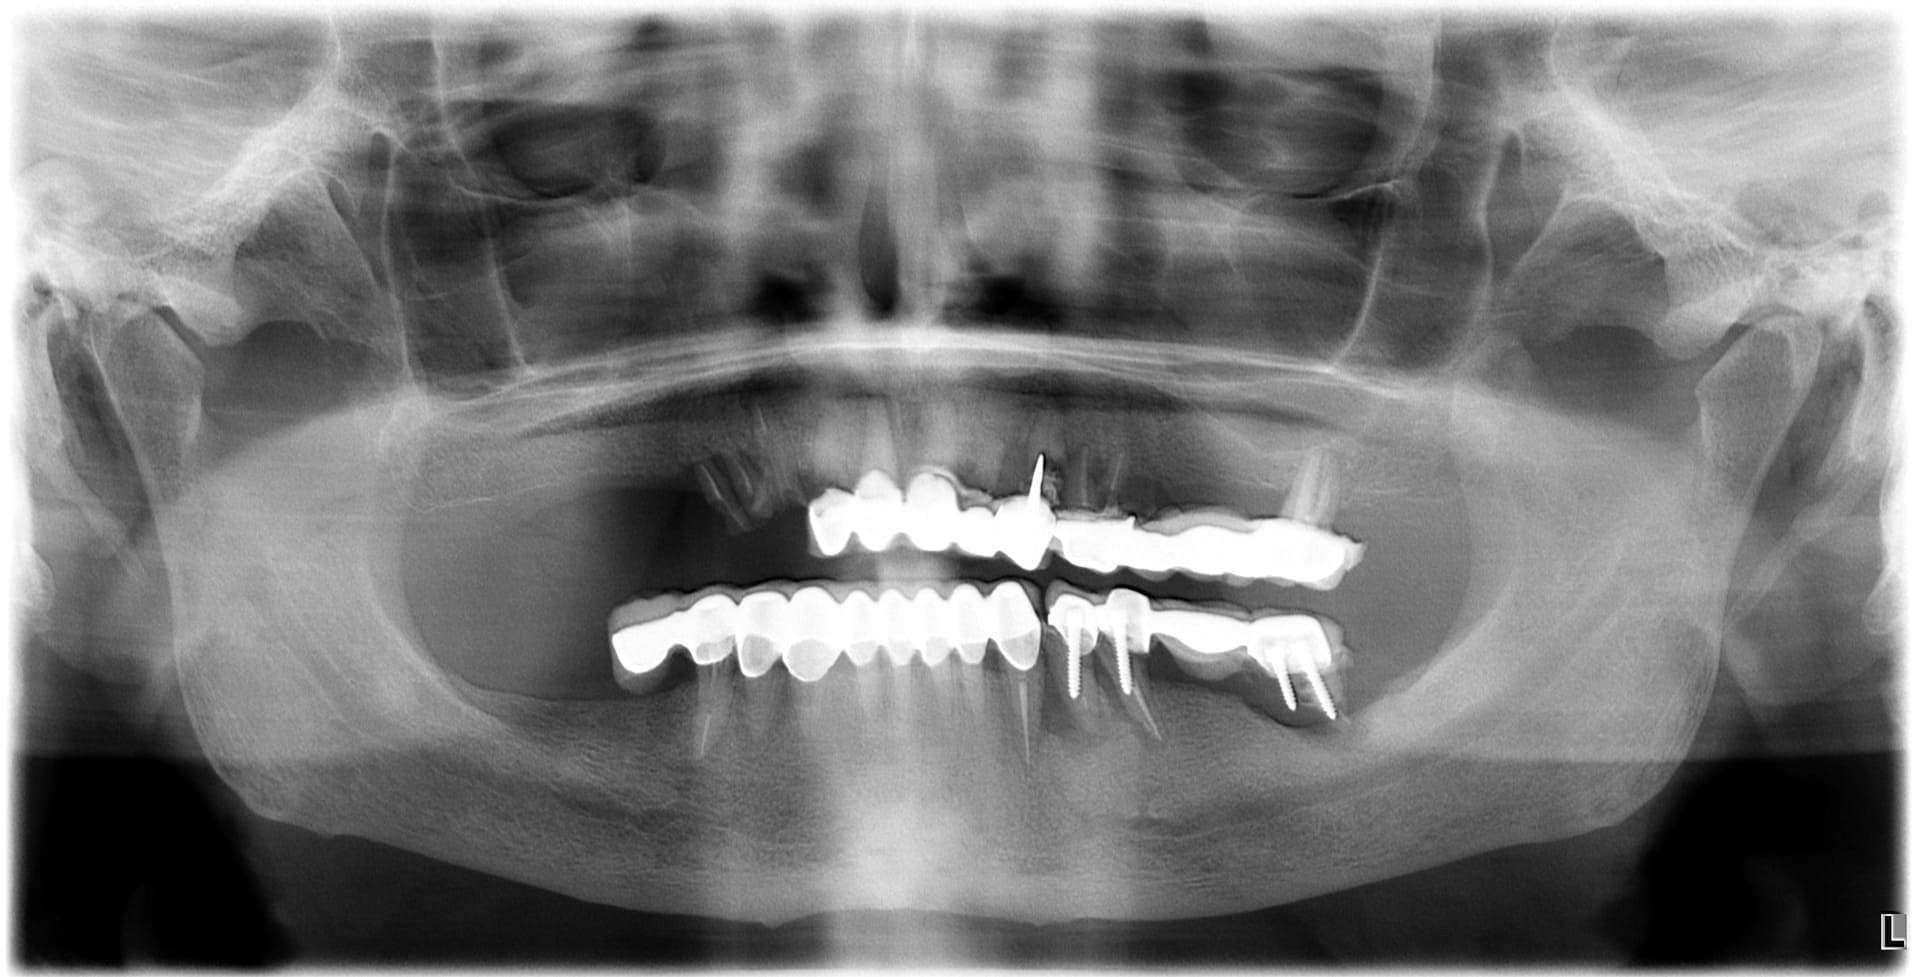

Casi clinici

Paziente 2

< Prima

Dopo >